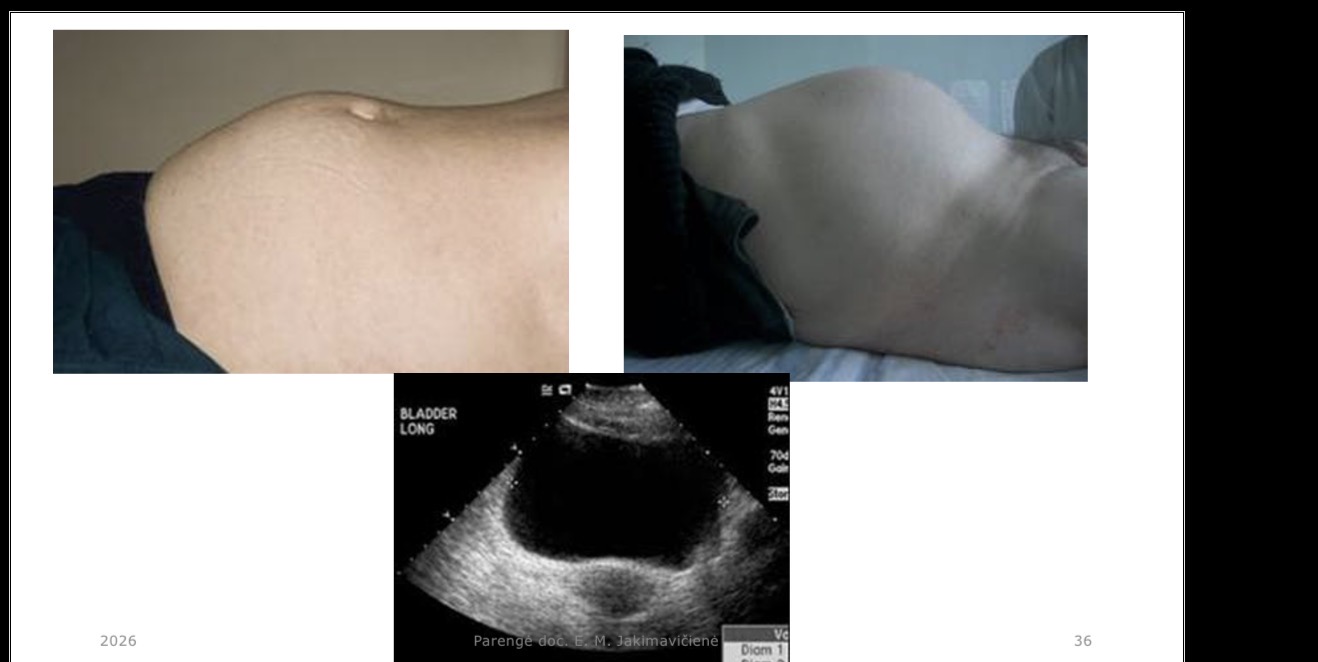

Šlapimo pūslės punkcija – kur atliekama?

Virš symphysis pubica

Šlapimo pūslės punkcija – kokia sąlyga suaugusiesiems?

Pūslė turi būti pilna

Kuo skiriasi šlapimo pūslės padėtis suaugusiems ir vaikams?

Suaugusiems – dubens organas (pilvo ertmėje tik kai prisipildžiusi); mažų vaikų šlapimo pūslė yra pilvo ertmėje

Kada atliekama šlapimo pūslės punkcija (o ne kateterizacija)?

Punktuoti tenka tada, kai yra pažeista šlapinimosi landa (šlaplus); jei laisva šlaplus – pūslę kateterizuoja